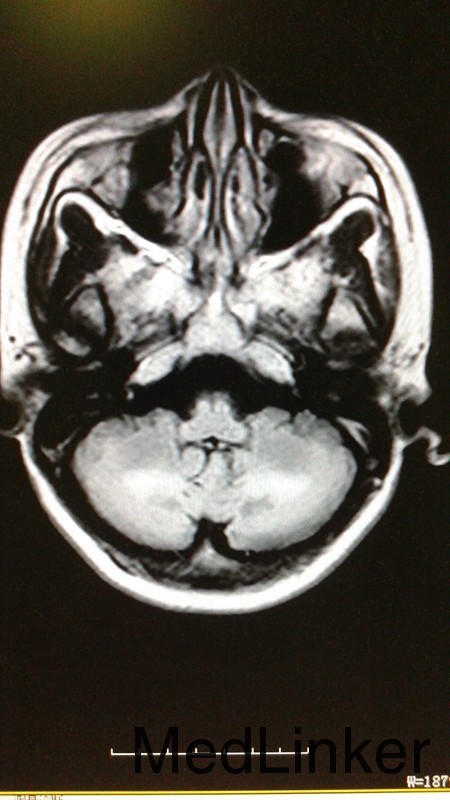

患者,女,44岁。主因反应迟钝,行走不稳4年,加重伴吞咽困难8月 患者4年前无明显诱因出现表情淡漠、反应迟钝,不与人交流,嗜睡、懒动、乏力,不修边幅,期初不影响生活未予诊治。此后上述症状逐渐加重,与人交流日渐减少,嗜睡,至两年前逐步出现行走左摇右摆,言语表达含糊不清,难以胜任日常生活,遂入院治疗,期间行头颅MRI示:1、双侧小脑齿状核、大脑脚及皮质脊髓束对称性异常信号。行跟腱检查结果示:左足纤维组织内查见结晶炎物及泡沫细胞,右足跟腱组织活检病理诊断:纤维结缔组织可见较多胆固醇裂隙、多核巨细胞形态符合黄色瘤,给予熊去氧胆酸片口服后病情好转出院。症状有所改善。服药期间自行停药。8个月前无明显诱因出现言语不利,行走不稳症状再次加重,双下肢僵硬、无力,行走不稳,需与人搀扶,遂再次入院。